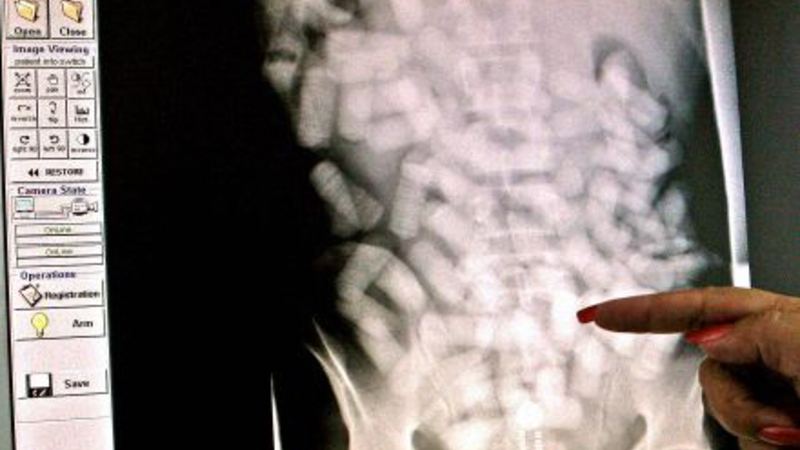

Det er tydeligt at se poserne med narko på scanningsbilleder

Skat kan ikke oplyse, hvordan de spotter smuglerne, fordi det kan give bagmændene gode idéer. Men tolderne sender alligevel en advarsel til smuglerne. Til foråret anskaffer Skat nemlig en kropscanner, der på stedet kan afsløre smuglere med stoffer under huden.

I dag sender toldere først mistænkte smuglere videre til politiet efter en afhøring. Politiet kører så den mistænkte til hospitalet, der scanner personen. I Billund Lufthavn har de som tidligere nævnt taget en enkelt smugler, der rejste fra Spanien, med et kilo kokain i år, men politiet er opmærksomme på, at en scanner i København kan starte en hel bølge af slugere til Billund.